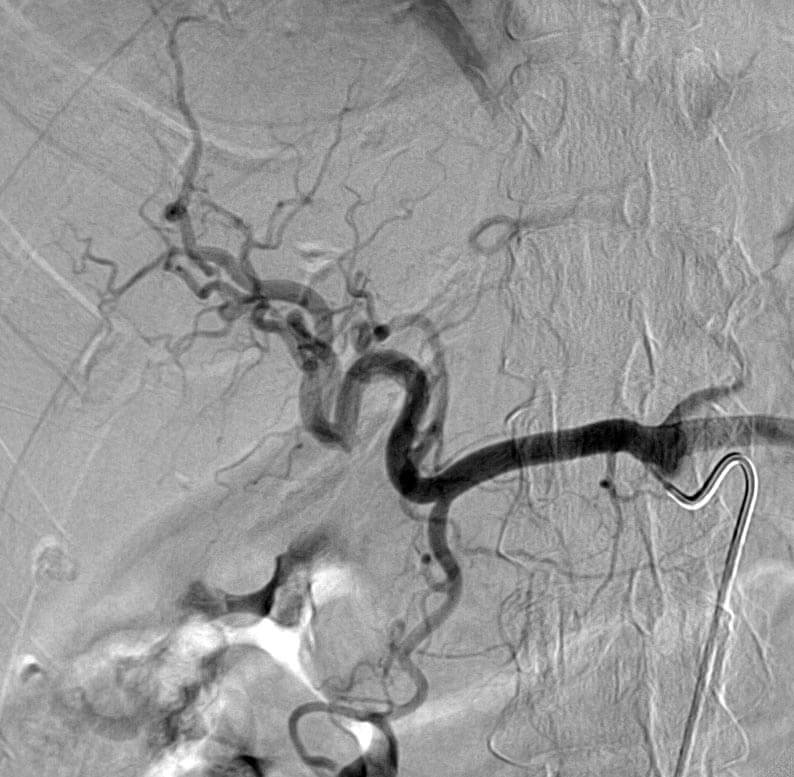

Radioembolization is a procedure used in the treatment of both primary tumors of the liver (such as hepatocellular carcinoma and cholangiocarcinoma) and metastatic disease involving the liver in diseases such as colon cancer, neuroendocrine tumors, breast cancer, etc. The procedure involves the administration of small radioactive microspheres (containing yttrium-90) directly into the blood vessels bringing blood into the tumors in the liver in order to expose those tumors to radiation.

Chemoembolization

Chemoembolization is performed by IR to treat primary tumors of the liver (such as hepatocellular carcinoma) and metastatic disease involving the liver (such as colon cancer, neuroendocrine tumor, thyroid cancer, etc.). The procedure involves the administration of small microspheres and chemotherapy directly into the blood vessels bringing blood into the tumors in the liver. These beads allow for the slow release of chemotherapy into the tumor for prolonged treatment.